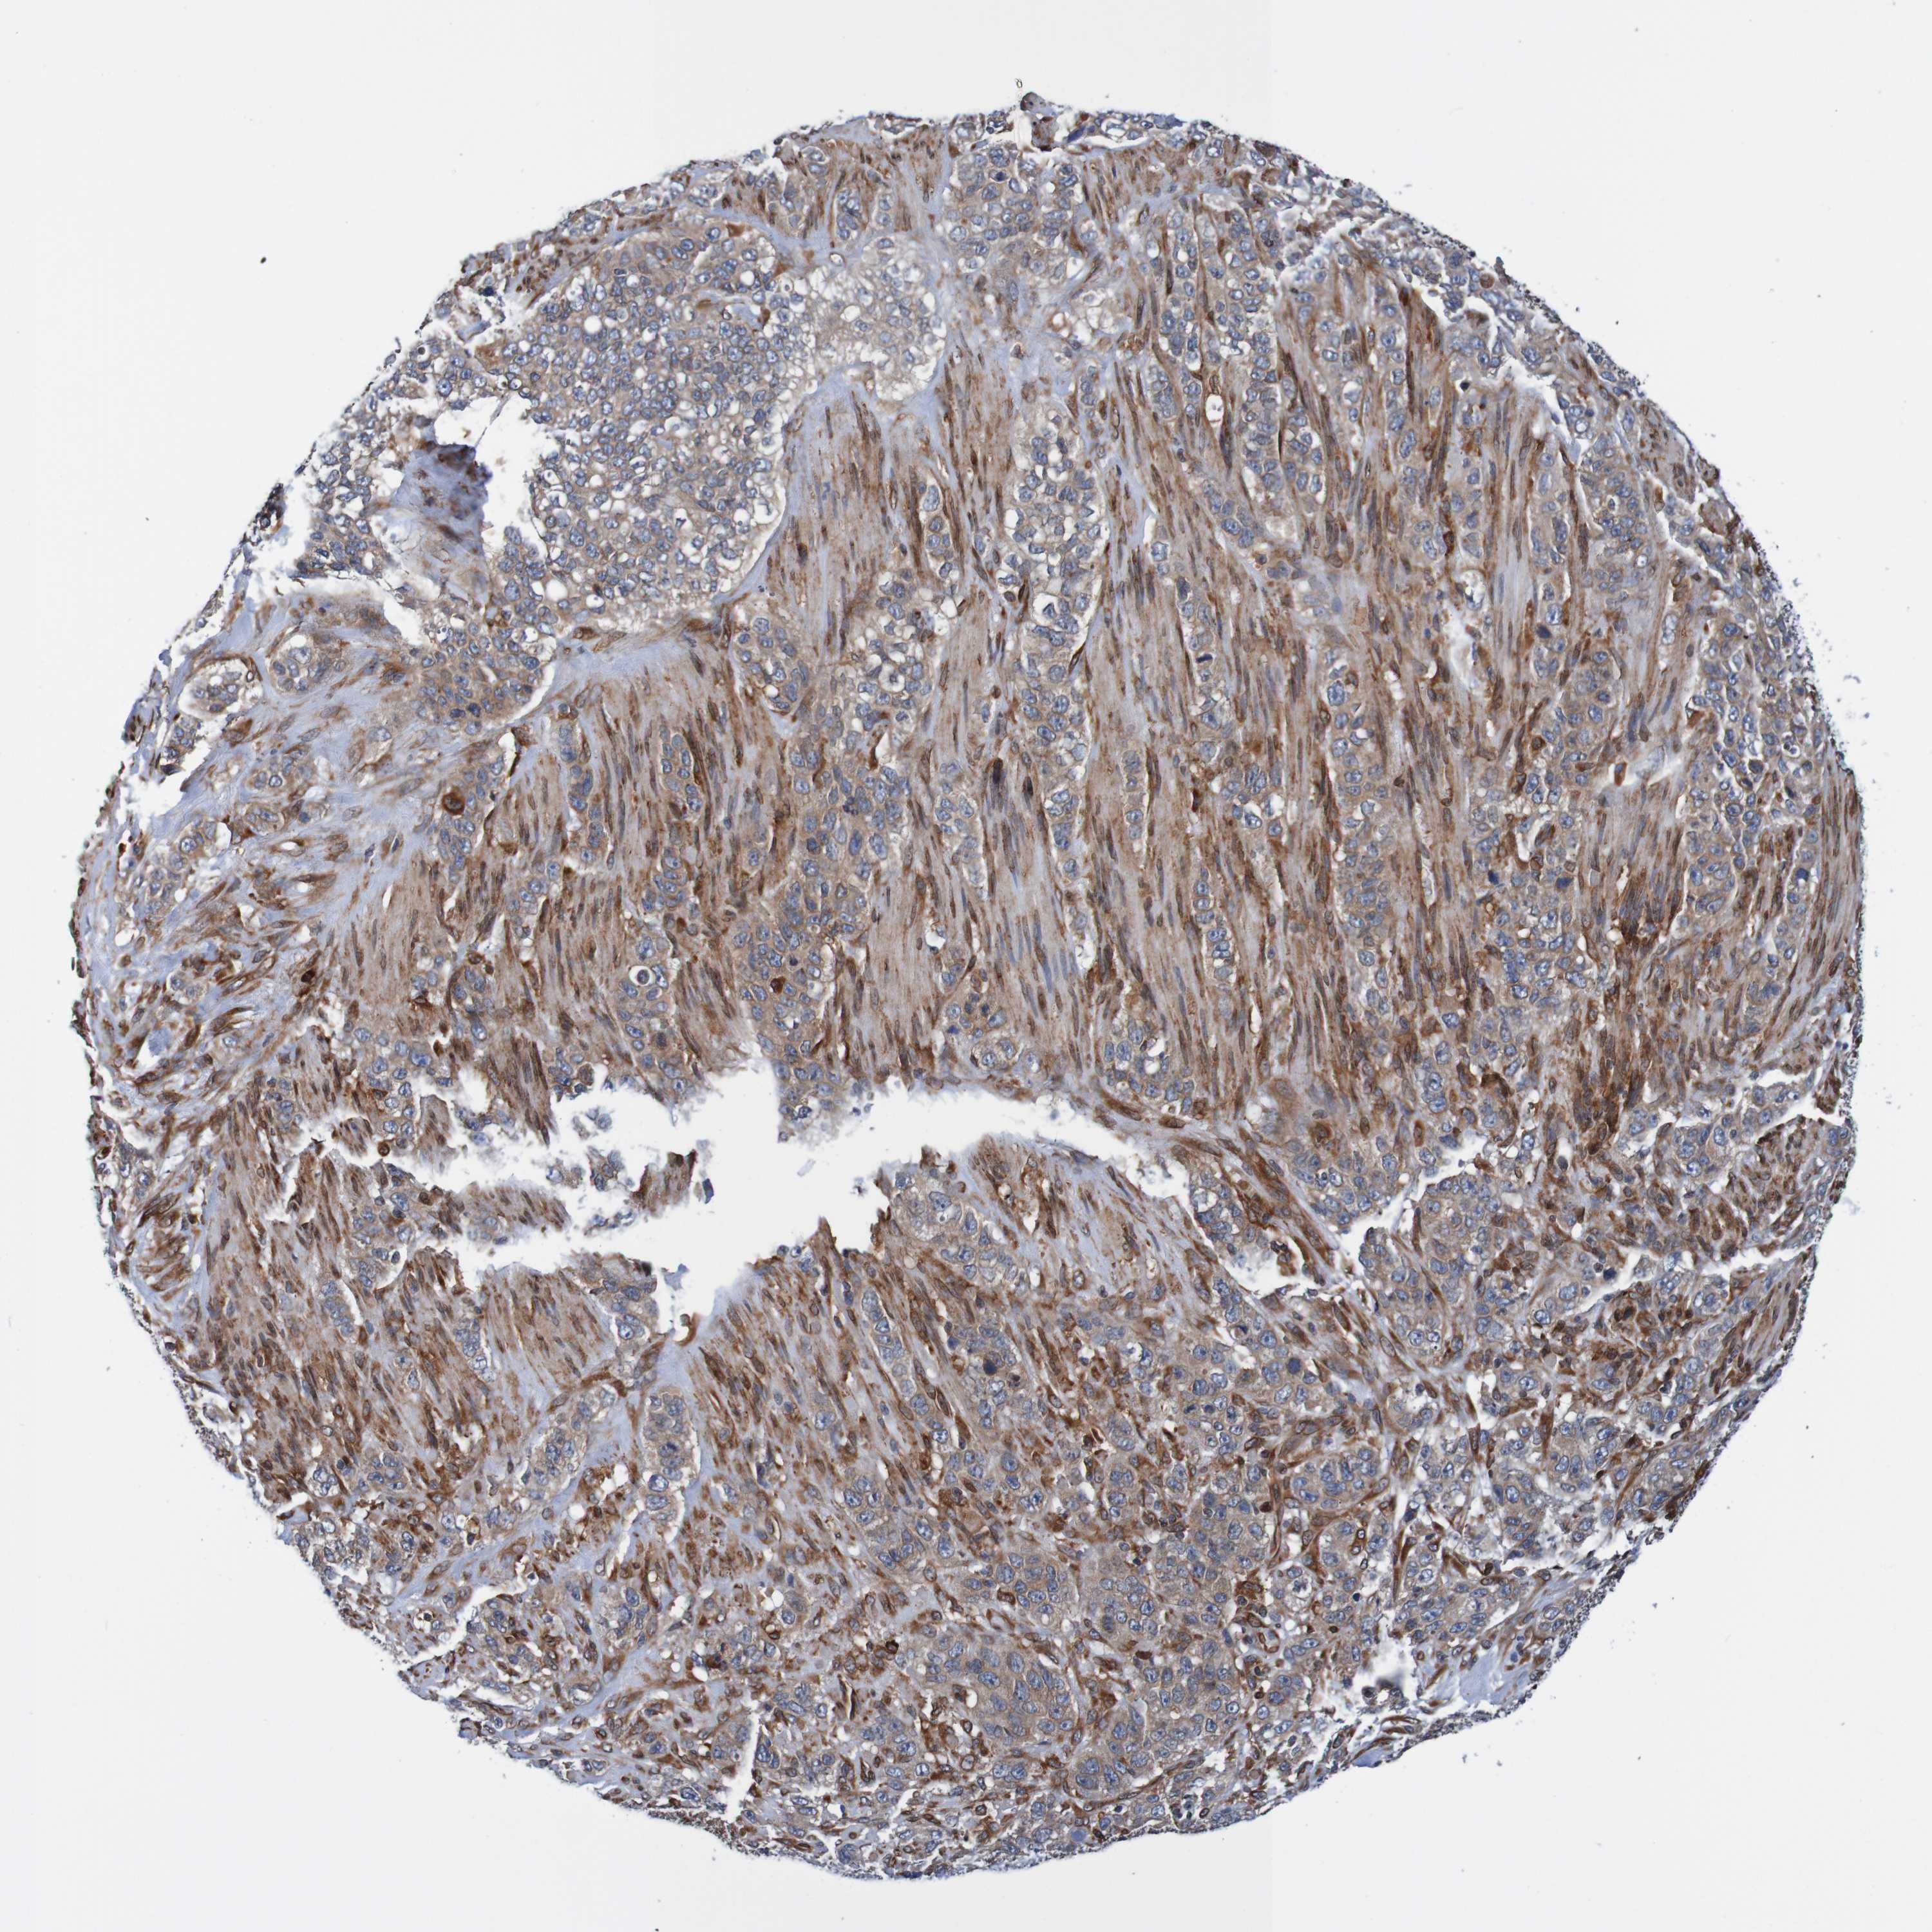

STOMACH CANCER - Protein expressioni

A mouse-over function shows sample information and annotation data. Click on an image to view it in a full screen mode. Samples can be filtered based on level of antibody staining by selecting one or several of the following categories: high, medium, low and not detected. The assay and annotation is described here.

Note that samples used for immunohistochemistry by the Human Protein Atlas do not correspond to samples in the TCGA dataset.

Antibody stainingi

Antibody staining in the annotated cell types in the current human tissue is reported as not detected, low, medium, or high, based on conventional immunohistochemistry profiling in selected tissues. This score is based on the combination of the staining intensity and fraction of stained cells.

Each image is clickable and will lead to virtual microscopy that enables deeper exploration of all samples and also displays staining intensity scores, fraction scores and subcellular localization as well as patient and tissue information for each sample.

Antibody HPA011785

Staining

High

Medium

Low

Not detected

Intensity

Strong

Moderate

Weak

Negative

Quantity

>75%

75%-25%

<25%

None

Location

Nuclear

Cytoplasmic/membranous

Cytoplasmic/membranous,nuclear

Adenocarcinoma, NOS

Adenocarcinoma, High grade